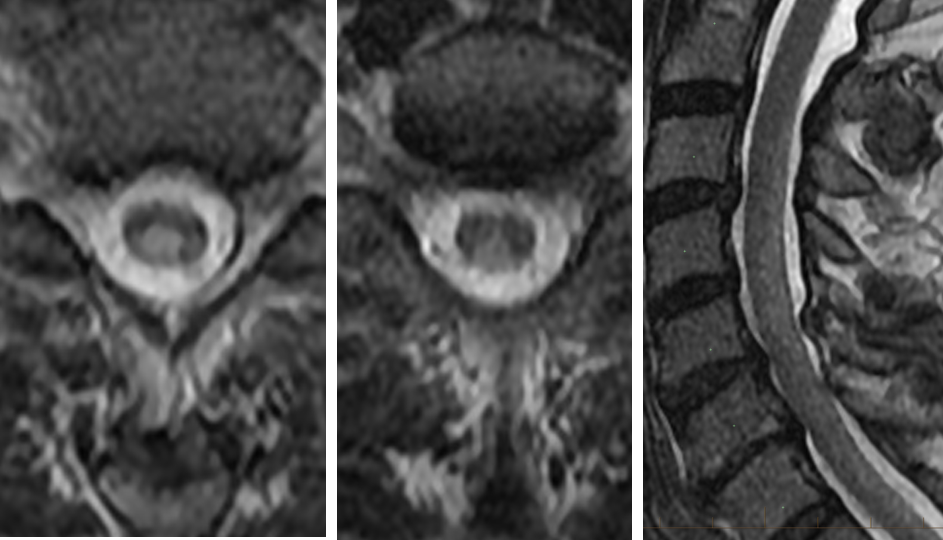

Spinal Mr Imaging In Vitamin B12 Deficiency Case Series Differential Diagnosis Of Symmetrical Posterior Spinal Cord Lesions Sen A Chandrasekhar K Ann Indian Acad Neurol

www.annalsofian.org